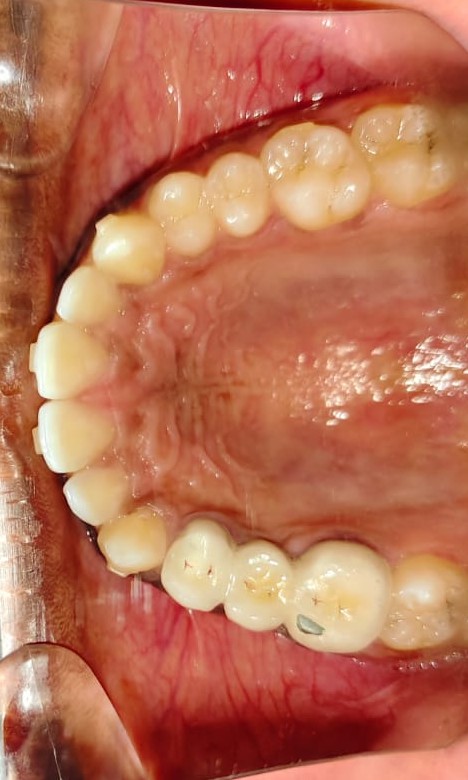

Sairam dental care located in Dharmapuri, with Leading Dentist In Oddapatti, is the Dental Hospital with exclusive root canal, Braces & Invisalign center. Led by renowned Drs Raghuraaman ( Periodontist) and Nivetha Raghuraaman ( Orthodontist) Sairam dental care offers gum treatment with expertise in laser, root canal treatment and digital smile correction with advanced technology aim to focus on aesthetics, comfort and precision. The clinic also specializes in Invisalign treatment, digital smile makeover, laser gum care, dental implants, root canal therapy, extractions and full-mouth rehabilitation blending compassionate care and clinical excellence.